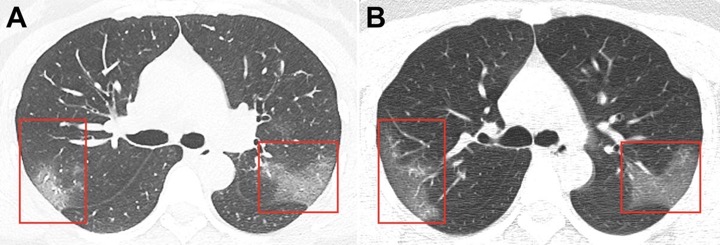

اسکن بیماران کرونا لکههای سفید رنگی دارد که رادیولوژیستها از آن به عنوان «کدورت شیشه مات» یاد میکنند.این علامت نشانگر عفونت شدید COVID-19 و ناشی از تجمع مایع در ریهها است. اما این علامت به تنهایی برای شناسایی ویروس کرونا مفید نیست. «این علامت در سایر عفونتها نیز قابل مشاهده است. عفونتهای باکتریایی، ویروسی یا حتی گاهی غیر عفونی و حتی در استعمال سیگار الکترونیک.»اما در مورد علائم ریه کرونا گرفته، لکه های قابل توجهی در سی تی اسکن ریه کرونایی هستند که تا لبههای ریههای بیمار امتداد مییابند. این چیزی نیست که خیلی شایع باشد. ما این مورد را در سندرم تنفسی حاد (SARS) و سندرم تنفسی خاورمیانه (MERS) مشاهده کردهایم.SARS و MERS هر دو از خانواده کرونا ویروس هستند.ریه و کرونا با هم مرتبط هستند و برای تست سلامتی ریه باید مطمئن شوید که دچار کرونا نشدهاید و یا اگر مبتلا شدید، کرونا را به سرعت مداوا کنید. شما از طریق درمانکده میتوانید تست کرونا در خانه یا محل خود بدهید و جواب را در ۲ روز کاری دریافت کنید:تجزیه و تحلیل نزدیک به ۱۴۰ اسکن ویروس کرونا نشان میدهد که «کدورت شیشه مات» در هر دو ریه از مشخصههای سی تی اسکن ریه کرونایی است.A: سی تی اسکن در روز پنجم ظهور علائمB: سی تی اسکن در روز نوزدهم ظهور علائم

محققان بیمارستان Zhongnan دانشگاه ووهان اسکن بیماران را تجزیه و تحلیل کردند. اکثر آنها مردان مسنی بودند که مشکلات زمینه ای داشتند. تصاویر بالا سی تی اسکن ریه کرونایی یک بیمار ۵۲ ساله است.اولین گروه اسکنها (گروه A) در ۷ ژانویه، پنج روز پس از شروع علائم در بیمار، انجام شد. «کدورت شیشه مات» در پایین هر دو ریه قابل مشاهده است.این مرد از ۷ تا ۱۲ ژانویه تحت درمان قرار گرفت. پس از آن، به نظر میرسید وضعیت او بهتر شده است. سری دوم اسکنها (گروه B)، که در ۲۱ ژانویه انجام شد، نشان می دهد که بسیاری از لکه های سفید کوچک یا ناپدید شده اند.وضعیت بسیاری از بیماران ویروس کرونا به سرعت وخیم و «کدورت شیشه مات» آنها پس از چند روز بارزتر میشود.وضعیت بسیاری از بیماران ویروس کرونا به سرعت وخیم و «کدورت شیشه مات» آنها پس از چند روز بارزتر میشود.وضعیت بسیاری از بیماران ویروس کرونا به سرعت وخیم و «کدورت شیشه مات» آنها پس از چند روز بارزتر میشود.